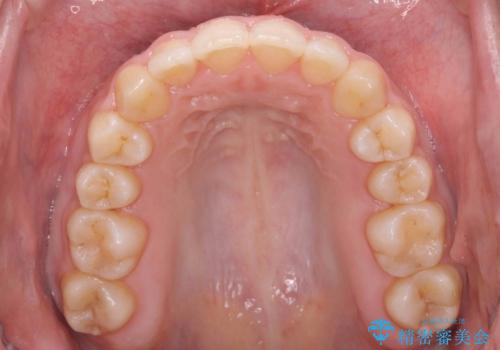

- 出っ歯を主訴に来院。

上の歯を全体に大きく後ろに下げる治療計画を立てました。

後ろに下げるために、親知らずは抜歯しています。